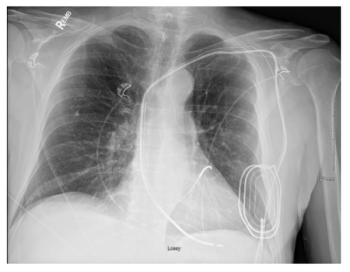

Study shows MRI exams can be safely performed with no adverse events in patients who have non-MR conditional devices, making the exams available for patients who frequently needs these studies the most.